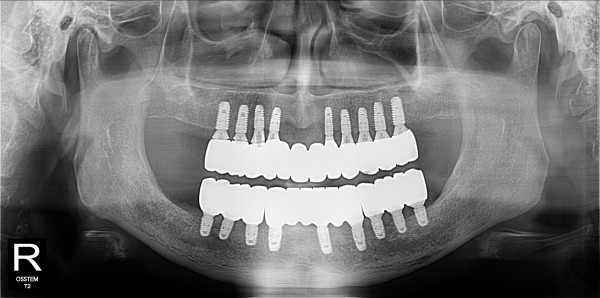

네비게이션 임플란트 최고관리자 0건 23-11-07 18:37 본문 무치악 네비게이션 임플란트 목록 이전글네비게이션 임플란트 23.11.07 다음글구치부 임플란트 23.11.07 댓글목록 0 댓글목록 등록된 댓글이 없습니다.